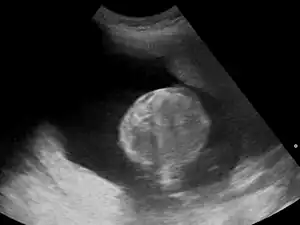

Polyhydramnios is a medical condition describing an excess of amniotic fluid in the amniotic sac. It is seen in about 1% of pregnancies.[1][2][3] It is typically diagnosed when the amniotic fluid index (AFI) is greater than 24 cm.[4][5] There are two clinical varieties of polyhydramnios: chronic polyhydramnios where excess amniotic fluid accumulates gradually, and acute polyhydramnios where excess amniotic fluid collects rapidly.

Diagnosis

During the pregnancy, certain clinical signs may suggest polyhydramnios. In the mother, the physician may observe increased abdominal size out of proportion for her weight gain and gestation age, uterine size that outpaces gestational age, shiny skin with stria (seen mostly in severe polyhydramnios), dyspnea, and chest heaviness. When examining the fetus, faint fetal heart sounds are also an important clinical sign of this condition.